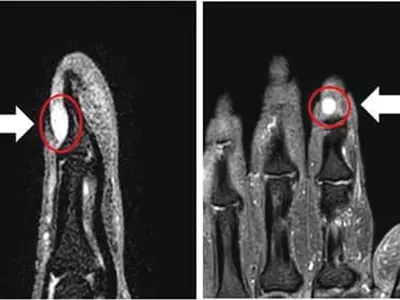

종양 작아 MRI로만 진단30분 내 간단수술로 치료 손톱이나 발톱에 차가운 물이 닿거나 살짝 눌리기만 해도 극..